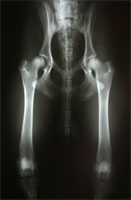

HD luxierte Oberschenkelköpfe

Abbildung 3 a: Vollständig luxierende dysplastische Hüftgelenke

DBO bei luxierten Femurköpfen

Abbildung 3 b: Der selbe grenzwertige Patient nach DBO und Unterstützungsband nach Meij.